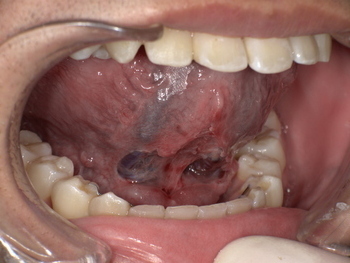

施術: 短くなった舌小帯をメスで切除・形成します。通常、約15分で完了する安全性の高い小手術です。

舌小帯形成術後、舌の動きがスムーズになり、上あごにしっかりと届くようになりました。これにより、発音に必要な舌の動きが改善されます。

舌小帯形成術は安全な治療ですが、術後に出血や腫れ、まれに再癒着が起こる可能性があります。これらのリスクについては、カウンセリング時に丁寧にご説明します。